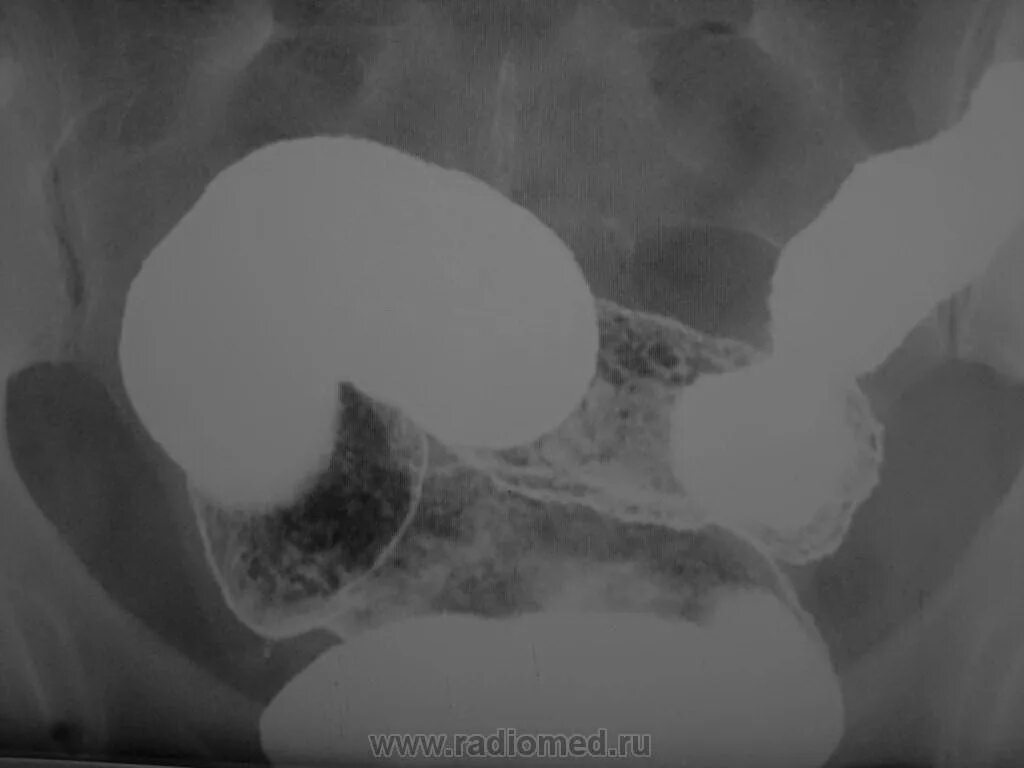

Ирригоскопия как проводится видео